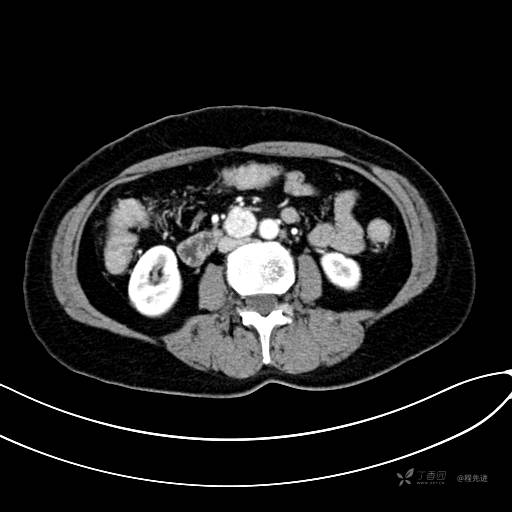

CT平扫